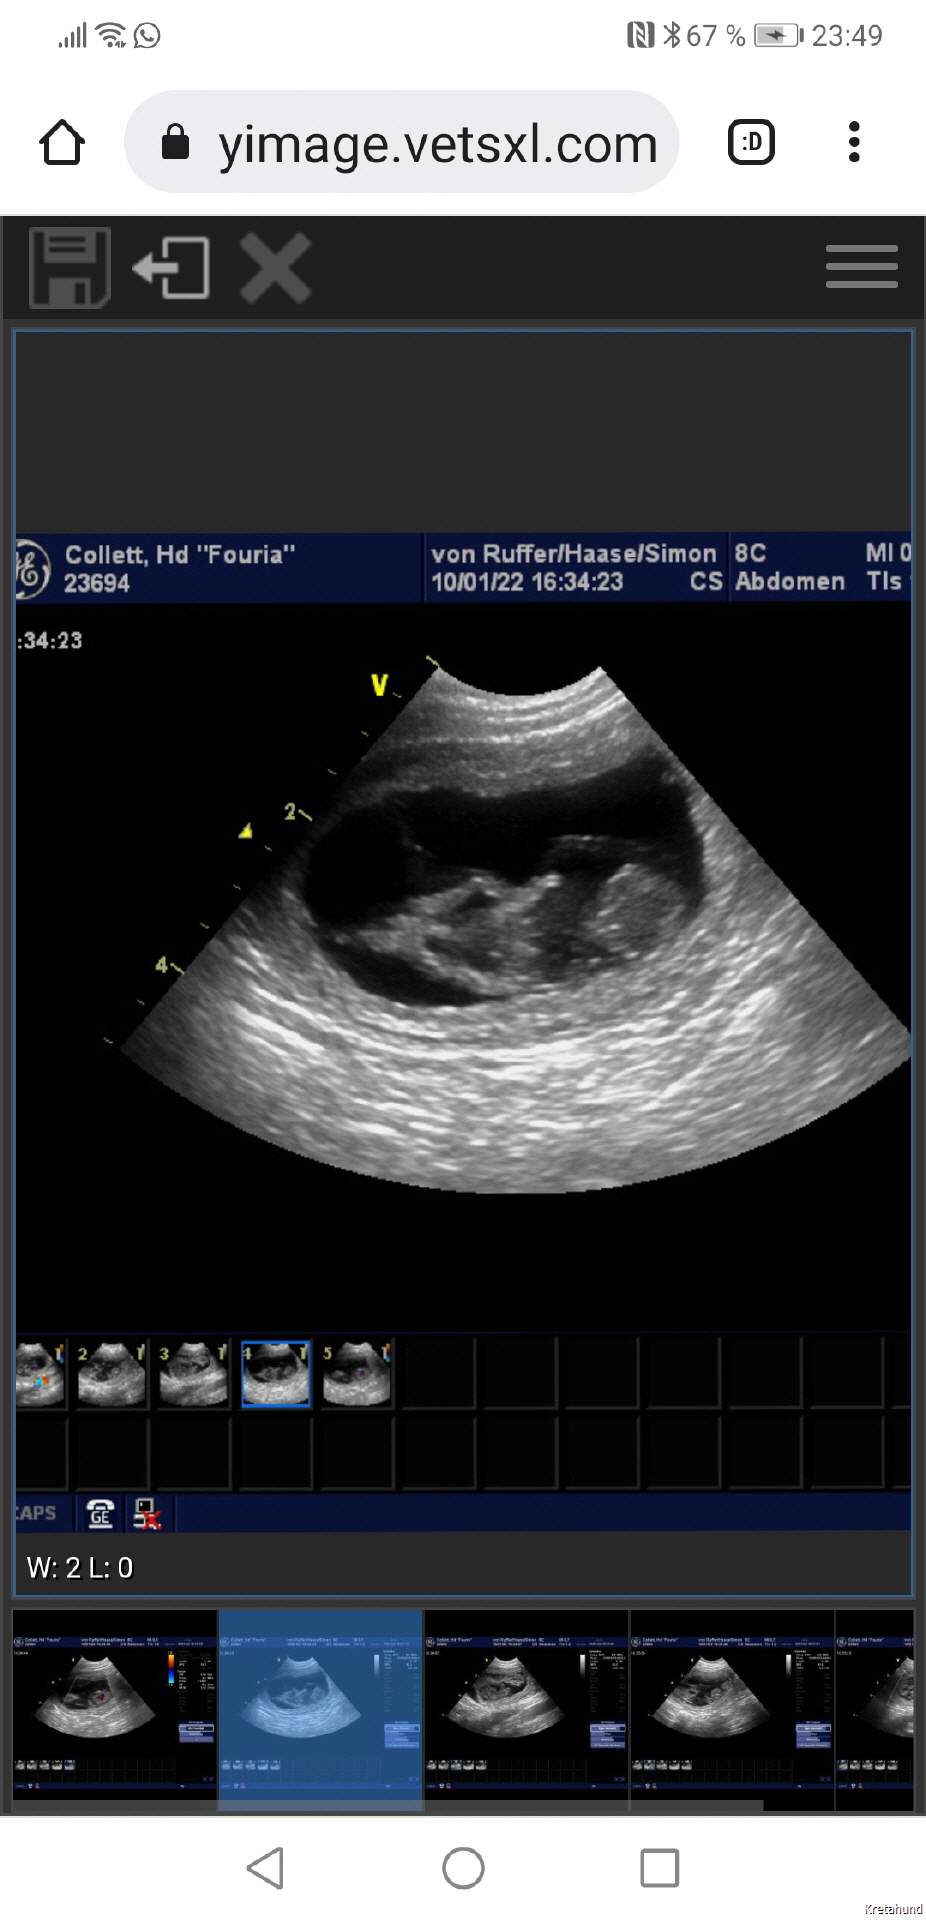

Ultraschall 5. Woche

Am 10. Januar 2022 war es offiziell: Fouria wird Mama!

Bei der Ultraschalluntersuchung in der 5. Trächtigkeitswoche konnten wir die kleinen Kritikoi das erste Mal sehen. Alles verlief prima, Fouria war topfit. Der voraussichtliche Wurftag war um den 11. Februar 2022 herum.